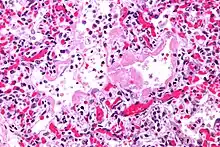

| Micrograph of diffuse alveolar damage, the histologic correlate of acute interstitial pneumonitis. H&E stain. | |

Rapid progression from initial symptoms to respiratory failure is a key feature. An X-ray that shows ARDS is necessary for diagnosis (fluid in the small air sacs (alveoli) in both lungs). In addition, a biopsy of the lung that shows organizing diffuse alveolar damage is required for diagnosis. This type of alveolar damage can be attributed to nonconcentrated and nonlocalized alveoli damage, marked alveolar septal edema with inflammatory cell infiltration, fibroblast proliferation, occasional hyaline membranes, and thickening of the alveolar walls. The septa are lined with atypical, hyperplastic type II pneumocytes, thus leading to the collapse of airspaces. Other diagnostic tests are useful in excluding other similar conditions, but history, X-ray, and biopsy are essential. These other tests may include basic blood work, blood cultures, and bronchoalveolar lavage.